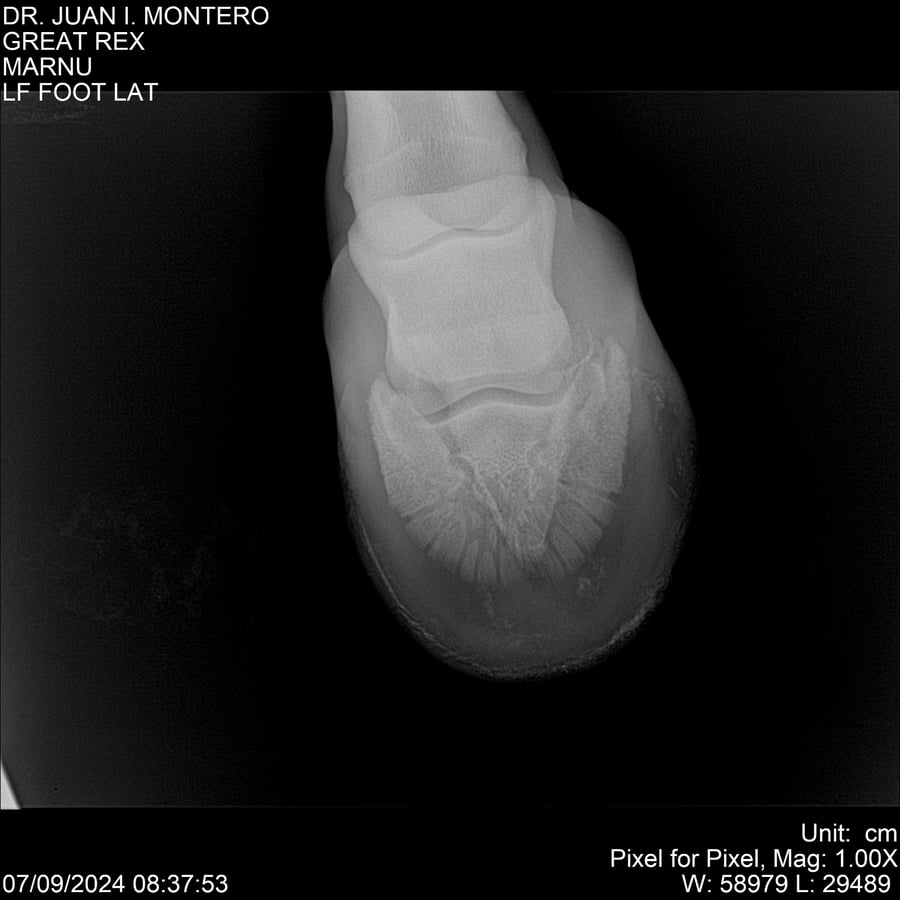

LOTE 4, GREAT REX Lote Anterior Volver al remate Lote Siguiente Ficha Contacto Montevideo - Ficha del Lote Identificador: #282518 Categoría: Yeguarizos Montevideo - 66 Visualizaciones ClicData Contacto Empresa: Abelenda N. R., Walter Hugo Nombre*: Teléfono* : E-mail* : Mensaje Enviar Registrese gratis Este contenido Exclusivo está disponible sólo para usuarios registrados Ingresar